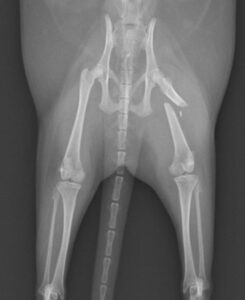

大腿骨骨折のフェレットちゃんの手術依頼でご紹介がありました。TAITAN1.2プレートを使用し無事歩けるようになりました。よかったね。